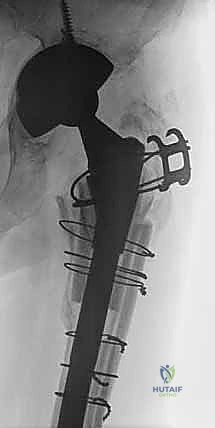

في حالات فقدان العظم الشديد أو صعوبة إزالة المفصل القديم، قد يلجأ الدكتور هطيف إلى تقنية متقدمة تُعرف بـ "قطع العظم المدوري الممتد" (Extended Trochanteric Osteotomy - ETO). يتم فيها شق جزء من عظم الفخذ طولياً لفتح القناة العظمية، مما يسهل إزالة المفصل القديم بأمان تام دون كسر العظم، ويوفر رؤية ممتازة لتحضير القناة للمفصل الجديد.

الخطوة الرابعة: زراعة الساق المخددة والتجربة

يتم إدخال الساق المخددة المصنوعة من التيتانيوم وتثبيتها بالطرق برفق حتى تنحشر بقوة في العظم السليم. إذا تم استخدام ساق معيارية (Modular)، يتم تركيب أجزاء تجريبية علوية لاختبار حركة المفصل، التأكد من عدم قابليته للخلع، وضبط طول الساقين ليكون متساوياً.

الخطوة الخامسة: الترقيع العظمي والإغلاق

إذا كانت هناك تجاويف عظمية كبيرة في الجزء العلوي من الفخذ، يقوم الدكتور هطيف بملئها بالطُعوم العظمية (Bone Grafts). إذا تم استخدام تقنية (ETO)، يتم إعادة إغلاق العظم المقطوع وتثبيته بأسلاك وكابلات معدنية قوية. أخيراً، يتم إصلاح العضلات والأنسجة الرخوة بدقة، وإغلاق الجرح تجميلياً.